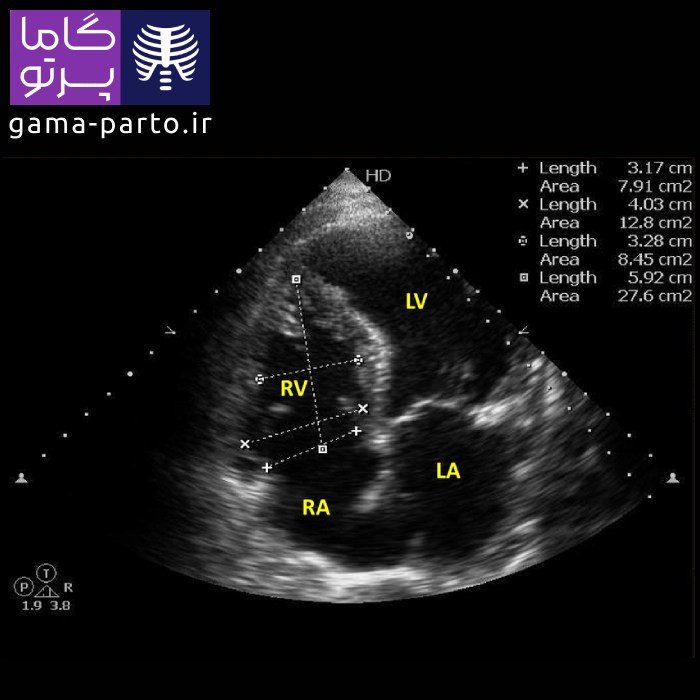

اکوکاردیوگرافی دو بعدی - Two Dimensional Echocardiogram

اکو قلب دو بعدی یکی دیگر از روشهای اصلی است که در اغلب کلینیکهای تخصصی قلب و همچنین توسط مجموعه گاما پرتو در خدمت اکو قلب در منزل تهران انجام میشود. در این تکنیک، تصاویر بهصورت دوبعدی ثبت میشوند و امکان مشاهده ساختار کلی و عملکرد قلب را فراهم میآورند. هرچند ترکیب آن با داپلر یا سایر تکنیکها، اطلاعات جامعتر و دقیقتری درباره جریان خون ارائه میدهد.